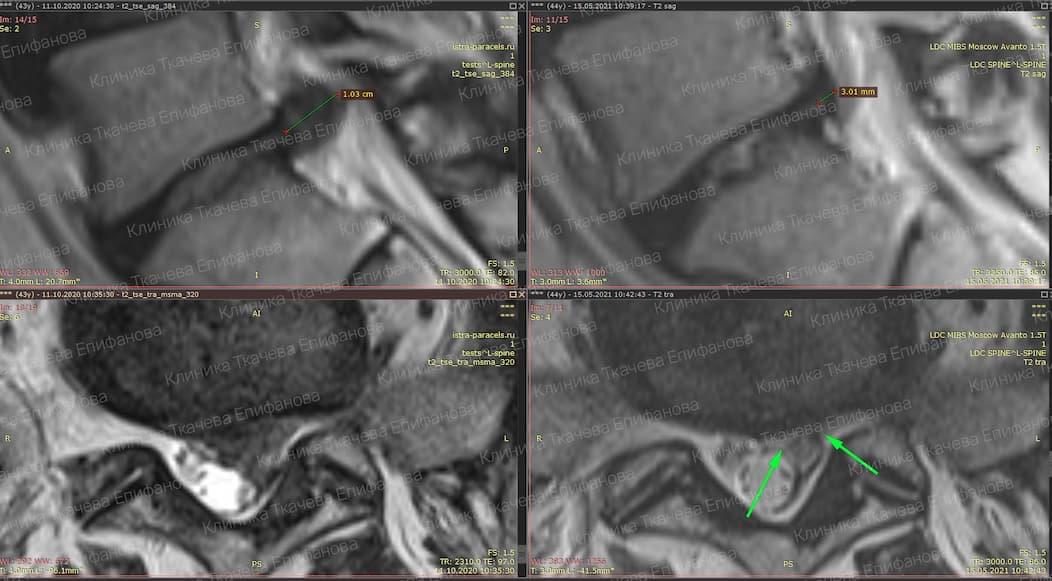

* Резорбция — процесс уменьшения грыжи диска за счет естественных физиологических способностей организма. Это основа эффективного лечения грыжи и альтернатива операции.

Метод модулируемой резорбции позволяет ускорить этот процесс, взять боль под контроль и улучшить качество жизни.